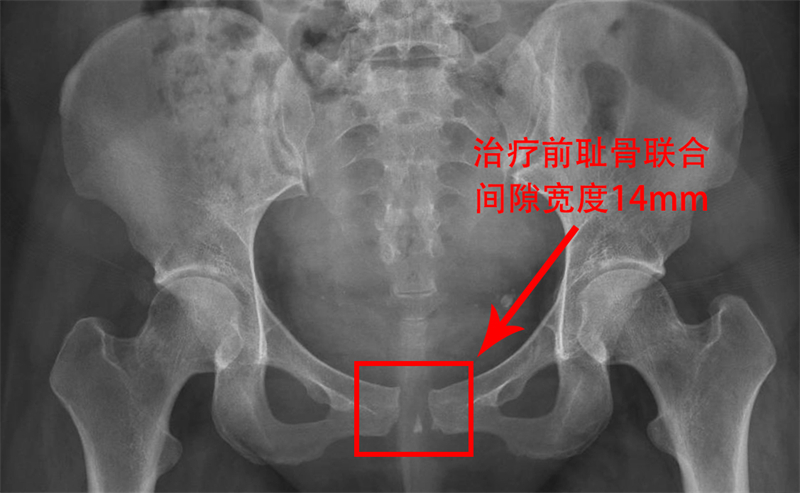

今年年初,刚经历分娩的麦女士在产后7天时,因耻骨区域剧烈疼痛,连简单的翻身、屈腿都变得异常艰难,更不用说正常行走了。在家人的陪同下,她坐着轮椅来到了柳人医盆底康复治疗区就诊。经过医生详细询问病史和查体,结合骨盆X光检查结果,麦女士被明确诊断为耻骨联合分离,分离程度达到了14mm。

耻骨联合分离,这个听起来有些陌生的名词,实际上在孕产妇中并不罕见。正常耻骨联合间距为4-5mm,妊娠期妇女生理性增宽3-7mm,而当分离程度>10mm时,即可诊断为耻骨联合分离。患者往往会出现耻骨联合、腹股沟区疼痛,活动受限,甚至出现摇摆步态。虽然其发生率仅为1/300-1/30000,但一旦发生,却会给宝妈们带来极大的痛苦和不便。

令人欣喜的是,经过5次治疗,麦女士的疼痛基本消失,行走自如,无摇摆步态。治疗后4月余复查骨盆X光显示,耻骨联合已经无分离,且没有出现反弹的情况。麦女士终于恢复了往日的活力,重新拥抱了健康的生活。